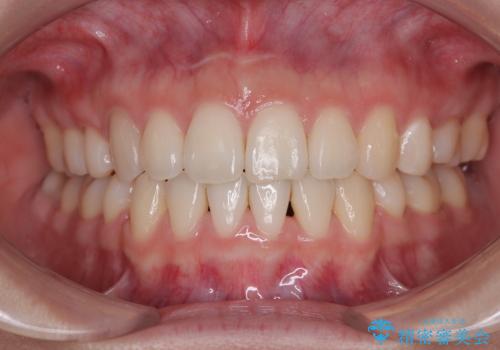

しみる前歯のセラミック治療 周辺も同時に治療して調和の取れた前歯に